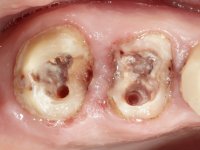

Teeth 17 and 16 were prepared for the fabrication of a 2-element Zr bridge. The impression was performed with a double mixing technique and a monolithic bridge in Zr was made in the laboratory. 4 years later, an abscess appeared in the apical area of tooth 26. It was decided to remove the bridge, remove the intra-radicular posts and retract the endodontic treatments of teeth 17 and 16. The removal of the bridge was carried out by making two cervical cavities. in the palatal area of the bridge and with a microluxator, disinsertion movements were performed. The intra-radicular posts were removed using fine drills and an ultrasound tip. The bridge was provisionally cemented and the patient was referred to a fellow endodontist for endodontic retreatment. After the retreatment, the intraradicular posts were placed again and the bridge was definitively cemented. One year later, a new abscess appears, possibly related to a root fracture. The bridge was sectioned between tooth 27 and 26 and tooth 26 was extracted and the crown of 27 was provisionally cemented. 3 months later, teeth 27 and 25 were prepared and a temporary bridge was made in dual polymerization resin. Then, an impression was made using the double mixing technique and a 3-element bridge in Zr was made in the laboratory. It was permanently cemented in the mouth with resin-reinforced glass ionomer cement.